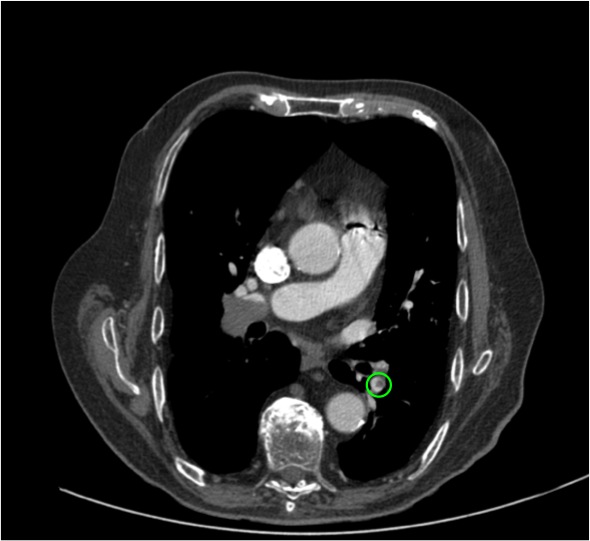

Cono de la pulmonar de calibre aumentado.

Cono de la pulmonar de calibre aumentado, indicativo de hipertensión pulmonar radiológica.

Relación VI/VD > 1. Signo de muy mal pronóstico.

Relación VI/VD > 1. El tabique interventricular está empezando a desviarse hacia el VI. Signos de muy mal pronóstico.